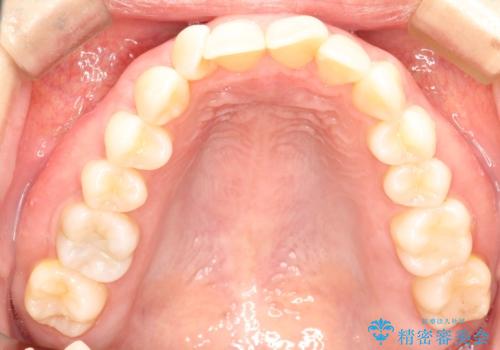

- 上の前歯のねじれを気にされて来院されました。

右上の前から2番目の歯が90度近くねじれて並んでいました。